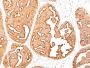

MCF-7 or MDA-231 cells. Breast, colon, ovarian, endometrial carcinoma.

Immunohistology formalin-paraffin 0.25-0.5 ug/mL|Staining of formalin-fixed tissues requires boiling tissue sections in 10 mM citrate buffer, pH 6.0, for 10-20 min followed by cooling at RT for 20 minutes|Flow Cytometry 0.5-1 ug/million cells/0.1 mL|Immunofluorescence 1-2 ug/mL|Optimal dilution for a specific application should be determined by user